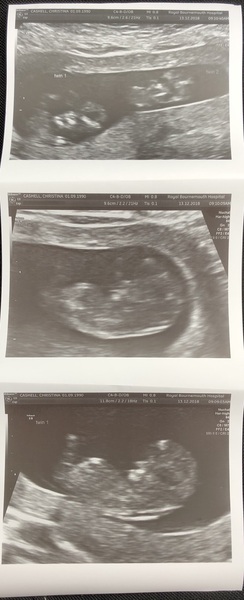

We had our scan yesterday too, all looking good and measuring bang on, I'm 13 weeks today so they confirmed my due date of 21st June. There was so so much information to take in! Our wee one was wriggling about loads, was so exciting to see ☺️

Ah lovely seeing everyone's scan pictures! And 2 ladies having twins - fab!